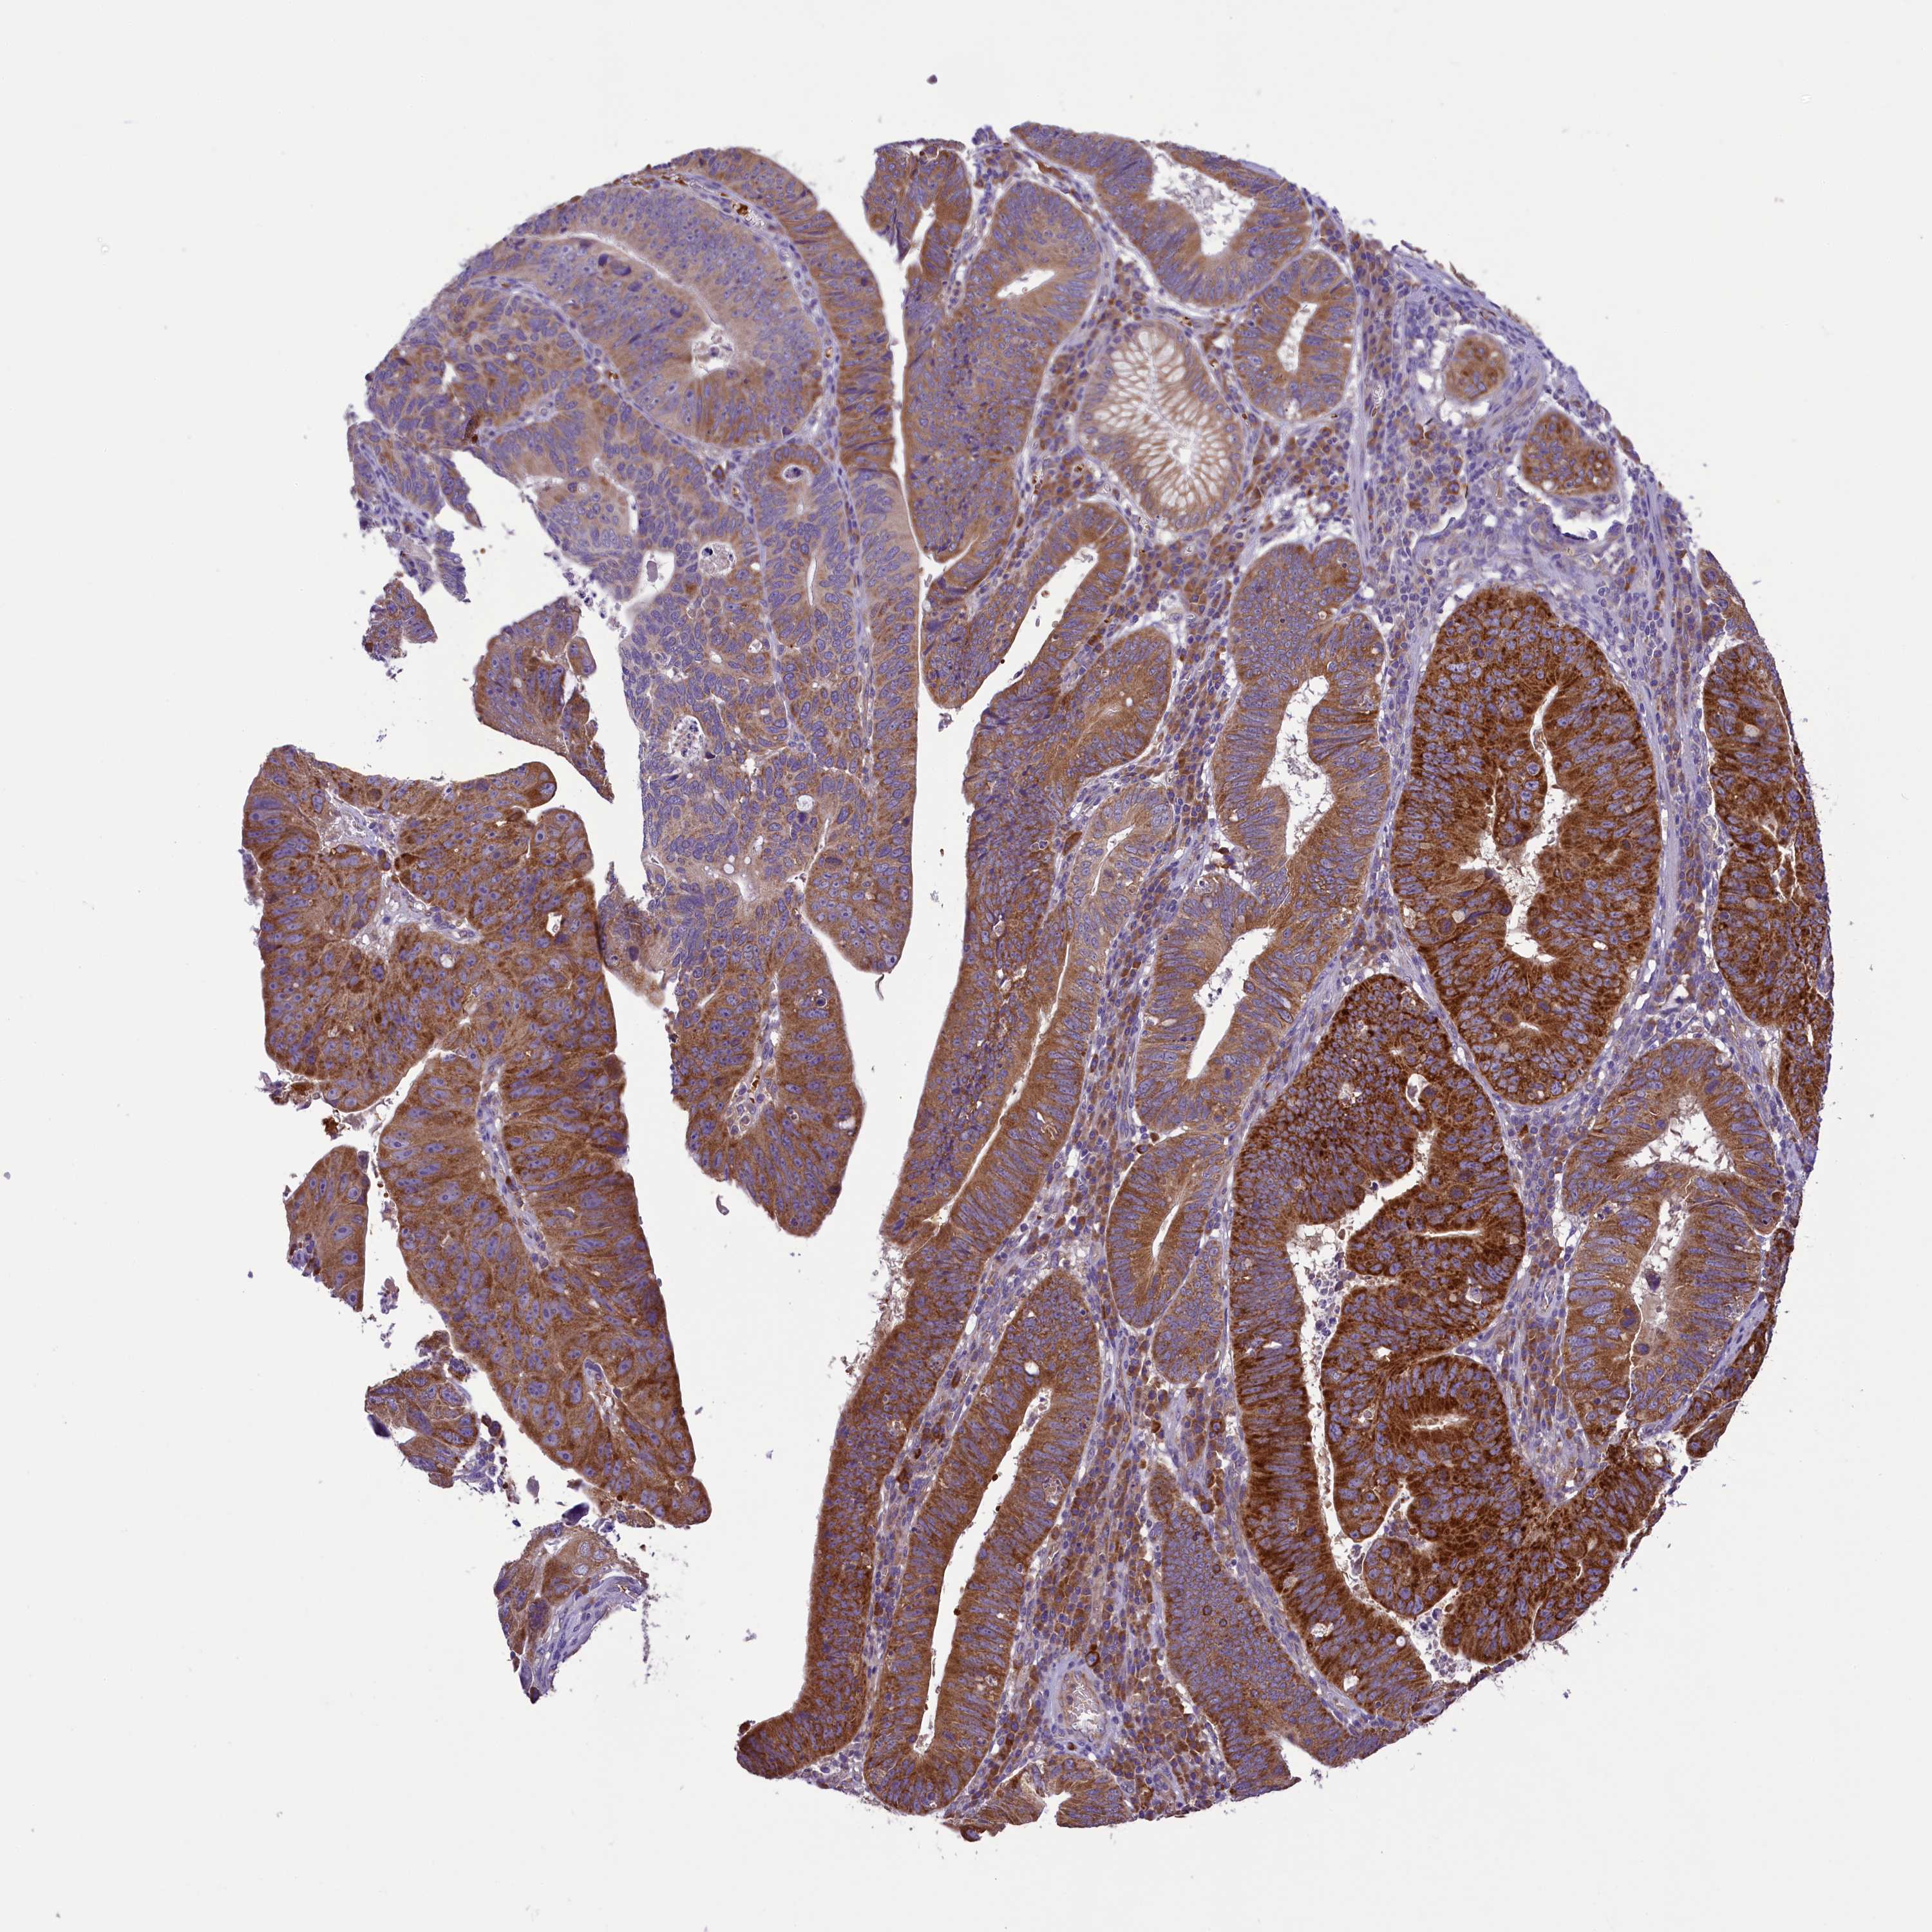

STOMACH CANCER - Protein expressioni

A mouse-over function shows sample information and annotation data. Click on an image to view it in a full screen mode. Samples can be filtered based on level of antibody staining by selecting one or several of the following categories: high, medium, low and not detected. The assay and annotation is described here.

Note that samples used for immunohistochemistry by the Human Protein Atlas do not correspond to samples in the TCGA dataset.

Antibody stainingi

Antibody staining in the annotated cell types in the current human tissue is reported as not detected, low, medium, or high, based on conventional immunohistochemistry profiling in selected tissues. This score is based on the combination of the staining intensity and fraction of stained cells.

Each image is clickable and will lead to virtual microscopy that enables deeper exploration of all samples and also displays staining intensity scores, fraction scores and subcellular localization as well as patient and tissue information for each sample.

Antibody HPA039306

Antibody HPA039673

Staining

High

Medium

Low

Not detected

Intensity

Strong

Moderate

Weak

Negative

Quantity

>75%

75%-25%

<25%

None

Location

Nuclear

Cytoplasmic/membranous

Cytoplasmic/membranous,nuclear

Adenocarcinoma, NOS